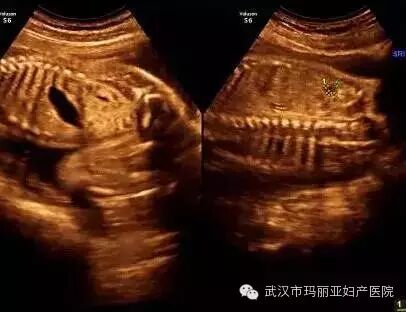

武汉玛丽亚妇产医院引进的世界领先的美国GE-E8四维彩超设备室目前世界上最先进、分辨率最高的彩色超声设备,具有即时立体成像、清晰准确的特点。

它能够多方位、多角度地观察宫内胎儿的生长发育情况,为早期诊断胎儿先天性体表畸形和发育异常提供科学依据。还能对胎儿的体表进行检查,如唇裂、脊柱裂、大脑、肾、 骨骼发育不良等,以便尽早的进行治疗。

玛丽亚美国GE-E8四维彩超排畸成功案例